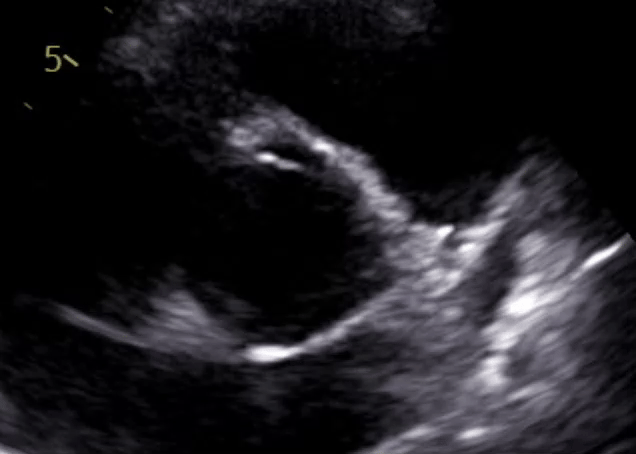

I also have a wealth of DICOM data from my echocardiograms; however, these are essentially series of videos. There isn't currently a trivial way to get these ingested and parseable in a useful way by existing LLM tools.

2D image -> 3D structure visualization

2D echocardiograms give planar views of the heart; what if we could convert these into 3D models? Modern techniques like photogrammetry are getting ever-better year on year; this feels like the sort of problem it only takes a sufficiently motivated engineer to piece together existing infrastructure to build...

DICOM analysis

(See the 'Gaps' section above) Analyzing these programmatically would likely need:

- Ability to ingest DICOM data

- Video ingestion pipeline for modern

- Pre-training on similar- imagery and their relevant diagnostic significance

- Analytical skill on which images to analyze, and specifically which parts to measure (e.g. left ventricular end-systolic diameter - when is the end of the systole? Between which points do I draw the line to calculate diameter?)

I can see parts 1- and 2- being already available; however, the volume of 3. in latest SOTA models is dubious at best, and 4. seems like it would need a dedicated fine-tuned approach given the specialized flow of analysis for each procedure. Not to mention, getting this pipeline to generate data with both sufficient accuracy to match that of current cardiologists is tough; now imagine the compliance/regulatory problems that might come with it...